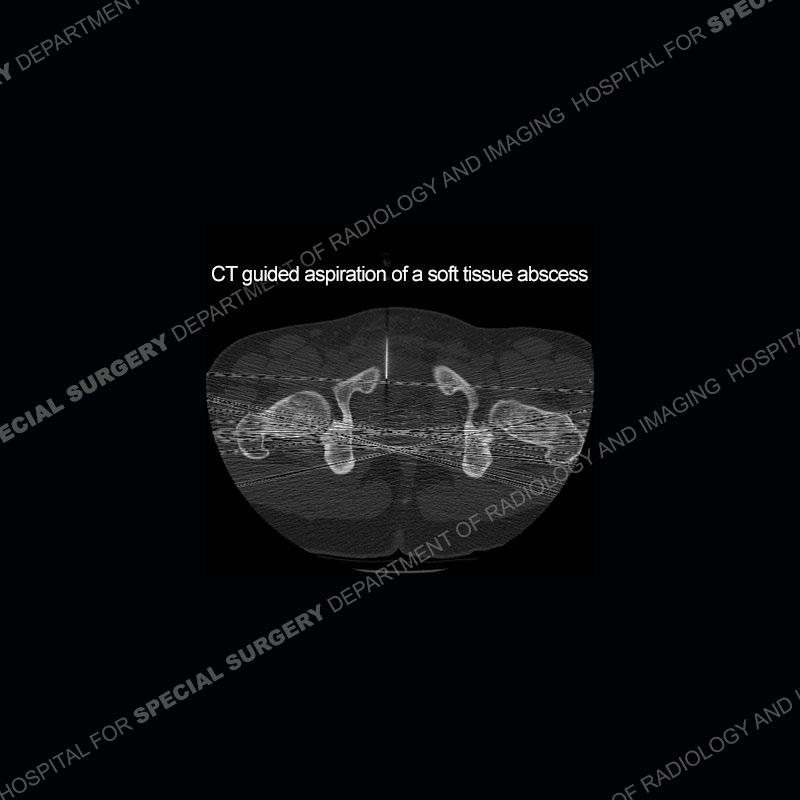

The repeat MRI, with the marked degree of increased abnormality of the bone and soft tissue shifted the diagnosis to a high degree towards infection. Even the most aggressive of neoplasms would not have that the degree of change in a 3-day time span. The CT study was shown before the repeat MRI but actually occurred just after the repeat MRI. It helped confirm the destructive process of the ramus and particularly the abnormal architecture along the inferior margin. The patient went on to have a CT guided aspiration of one of the soft tissue collections with 4cc of purulent fluid obtained. A surgical irrigation and debridement of the bone and soft tissue was performed. A PICC line was placed and the patient is currently undergoing IV antibiotic treatment with a possible repeat irrigation and debridement.